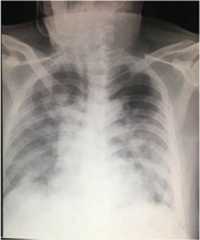

During illness days 9 and 10, his fever continued with occasional non-productive cough. He remained clinically stable apart from intermittent SpO2 desaturations of 93–97% on 2–3 L/min of oxygen. On illness day 11, he developed increasing dyspnoea with reduced SpO2 at 88% despite 8 L/min of oxygen via a face mask and haemoptysis and was noted to have bilateral chest crepitations. A chest radiograph was reported as showing hazy infiltrates in both lung fields consistent with pneumonia (Fig.4). Meropenem 2 g IV three times a day (TDS) was commenced.

Fig. 4.

Posteroanterior chest radiograph of patient 2, 27 January 2020 (illness day 10). Hazy infiltrates in both lung fields consistent with pneumonia